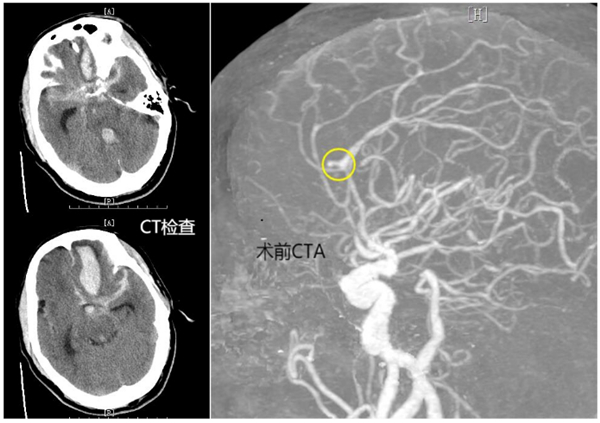

患者岑先生突发神志不清、呼之不应。恩平市120急救中心快速将患者从当地卫生院转至恩平市人民医院开展进一步救治,并提前开通生命绿色通道,完善初步CT检查,并收入ICU。根据患者病程及CT结果,恩平市人民医院神经外科诊断为颅内动脉瘤破裂出血。

时间就是生命,恩平市人民医院立即启动多学科联合诊疗应急处置预案,一方面由ICU快速行气管插管、呼吸机辅助呼吸、降颅压等治疗。同时,联合放射科、医学检验科、麻醉手术科、导管室等科室开放快速诊疗通道。急查头颈部CTA提示:左侧大脑前动脉瘤、左额叶大量脑出血破入脑室、蛛网膜下腔出血。

由于患者颅内动脉瘤破裂出血量极大,已陷入深度昏迷,Hunt-HessⅤ级,病情危重,时间紧迫。医生向患者家属告知病情,并建议尽快手术,将出血的动脉瘤进行栓塞,防止再度出血。

经和家属协商,同意进行手术。该院神经外科介入团队立即启动手术预案。麻醉医师、手术室护士、导管室医护等提前做好术前准备。麻醉成功后,先行脑室钻孔引流,为动脉瘤栓塞争取更多时间。而后,顺利找到了破裂出血的动脉瘤并完美致密填塞,出血情况得到控制。历经4个小时的救治,最终将患者从死亡边缘拉了回来。